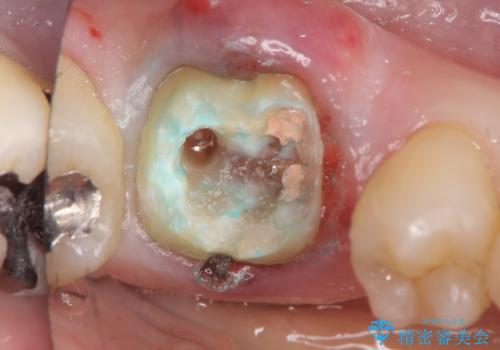

また、根の詰め物が根尖孔外(根の先の外の骨の部分)に盛大に漏れ出しており、歯周ポケットと根尖病巣が交通しているような状態でした。

被せ物を外したところ、歯が大変薄くなって割れており、残念ながら残すことはできないと説明しました。

初めての根の治療には見えないくらい、かなり歯が削ってあり、薄くなっていて割れても仕方ない状態でした。前の状態を見ていないので何とも言い難いですが、他の歯に比べこの歯だけ極端に状態が悪かったです。

当院は最後まで歯を残せるように、きちんと破折していないかチェックし、患者様に写真を確認していただいたうえで抜歯をするかを相談していきます。